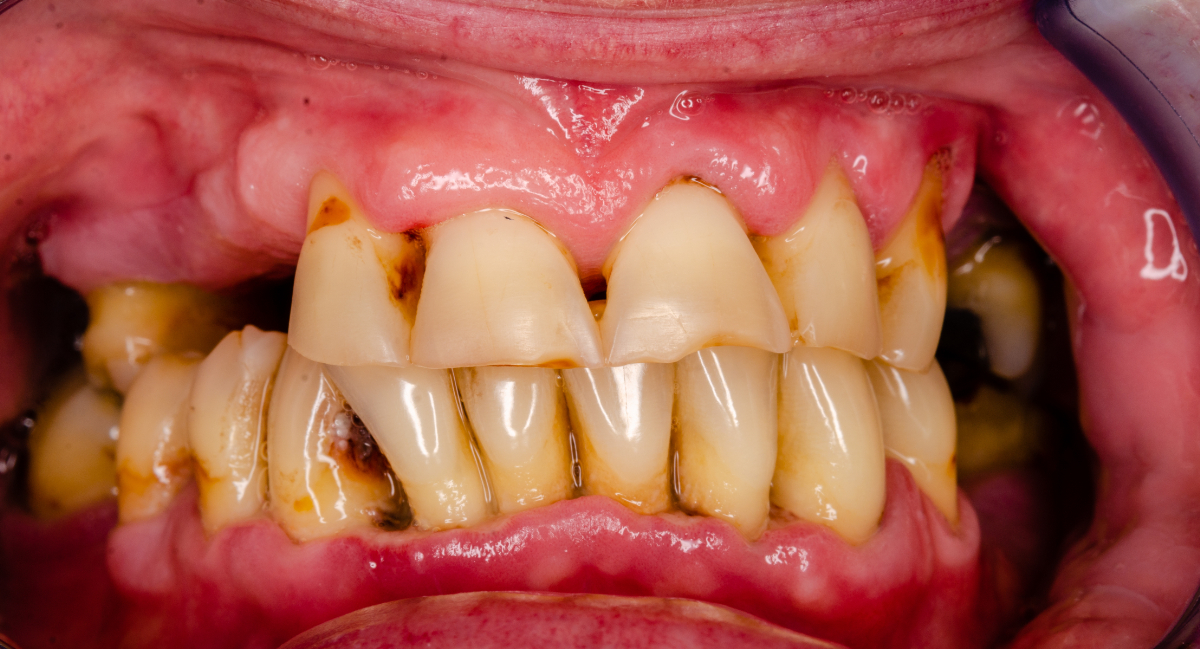

歯周病

歯周病は、歯を支えている歯ぐきやあごの骨が炎症を起こし、徐々に弱っていく病気です。

初期段階では自覚症状がほとんどないため発見が遅れるケースが多く、気づいたときにはすでに進行していることも珍しくありません。歯ぐきの腫れや出血、口臭などが見られる場合は、歯周病が進行しているサインです。

進行すると歯を支える骨が溶け、最終的には歯が抜け落ちることもあります。日本人が歯を失う原因として最も多いとされており、特に中高年以降に多く見られます。